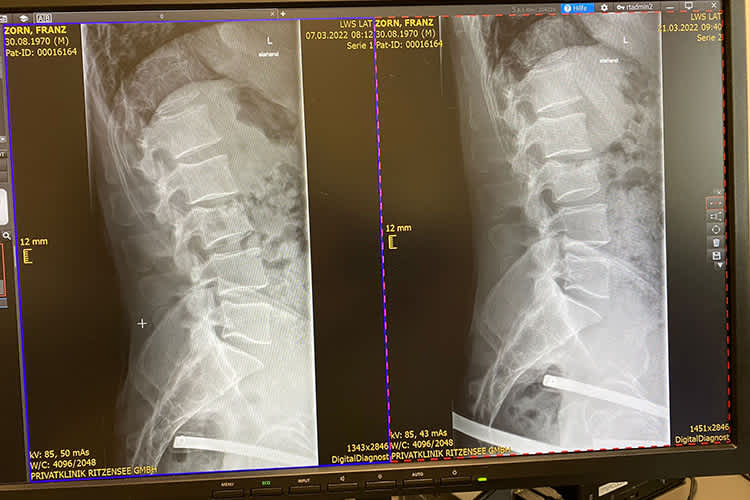

"Normalerweise stehst du nach so einem eigentlich harmlosen Sturz auf und fährst weiter. Wenn es der Renntag gewesen wäre, wäre es kein Problem gewesen", meinte Franky Zorn zum Regelfall. Doch solch einer war es leider nicht, was er im Detail folgendermaßen erläuterte: "Am Abend hatte ich schon starke Schmerzen im Fuß und habe mit Eis versucht, das zu beruhigen. Doch das hat alles nicht geholfen. Am nächsten Tag hatte ich keine Chance, in den Stiefel reinzukommen, sodass ich gleich am Samstagmorgen nach Hause aufgebrochen bin. Ich habe von unterwegs aus versucht, etwas in Sachen röntgen in die Wege zu leiten, aber das ist in der heutigen Zeit wohl wegen Corona nicht möglich. Es ist unglaublich. Am Sonntag war das Krankenhaus mit zwei Lehrbuben besetzt, die wussten von nichts. Somit habe ich erst am Montag einen Termin bekommen."

Bei diesem wurde glücklicherweise nur eine starke Prellung, aber kein Bruch diagnostiziert. Über den Hergang grübelt der 51-jährige Österreicher weiterhin, ohne zu einem schlüssigen Ergebnis zu kommen. "Es war ein unglücklicher Sturz, wobei ich mich heute noch frage warum? 15 Stürze in einem Rennen sind einfach unfassbar. Hinterräder rutschten weg, als wären keine Spikes drauf. Irgendetwas war da mit dem Eis, nur bin ich noch nicht dahintergekommen was. Dass ich im Training einen Sturz hatte, sehe ich nicht so negativ, weil mir das Training bis dahin Spaß machte. Das Motorrad ist gut gelegen und das Set-up hat gepasst. Und der Lausch-Motor geht sowieso wie die Sau. Somit haben wir trotzdem zumindest eine gute Resonanz bekommen. That’s racing. Man muss verlieren, um zu gewinnen. Kopf hoch, weiter geht es!" Seine weiteren Pläne kann der Saalfeldener nun zwar zeitversetzt, aber immerhin fortführen. Zu diesen sagte er gegenüber SPEEDWEEK.com: "Jetzt geht es eben ein paar Tage später nach Schweden. Ich denke, dass ich am Donnerstag hoch fahren werde. Am Anfang dürfte es eine Schmerztabletten-Sache werden, denn ich will das jetzt erst langsam aufbauen. Bis zum Wochenende vergehen noch ein paar Tage, dann sollte es passen. Geplant ist, dass wir bis zum 22. Dezember oben bleiben. Aber wenn es erforderlich ist, bleiben wir über Weihnachten und Neujahr. Am 6. Januar ist dann eh schwedische Liga in Örnsköldsvik und am 8. Januar in Strömsund. Da möchte ich schon gern mitfahren. Eigentlich will ich Weihnachten zu Hause sein, aber schauen wir mal."